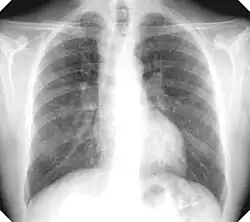

La silicosis simple es la forma clínica más frecuente con mucho. Muestra opacidades redondas (las más frecuentes) y/o irregulares en radiografía simple póstero-anterior de tórax (Rx). No suele producir alteraciones funcionales con significación clínica ni disminuye la esperanza de vida, siempre que no evolucione a complicada.

El diagnóstico se basa en una historia laboral significativa y hallazgos típicos en Rx. La OIT (Organización Internacional del Trabajo) ha elaborado una normativa con el fin de clasificar, describir y codificar las alteraciones radiográficas, atribuibles a neumoconiosis y facilitar su comparabilidad en estudios epidemiológicos, sin pretensiones o connotaciones legales, aunque también se usa en la clínica; la edición del año 2000 se basa en la comparación de la Rx del paciente con placas modelo que aporta la organización.[8]

Las pequeñas opacidades redondas se clasifican según su diámetro como p (las más pequeñas), q (las que exceden 1.5 mm) y r (las que exceden 3 mm y no pasan de 10 mm) y las irregulares como s, t, u en función de su anchura (equivalente al diámetro en las redondas). La cantidad o profusión se categoriza de 0 a 3.

Se establece una notación combinada en función de la profusión con 12 categorías desde 0/- (pulmón completamente limpio) 3/+ (la máxima profusión imaginable); por ejemplo 1/2 q/t. La primera cifra y la primera letra serían las más probables.